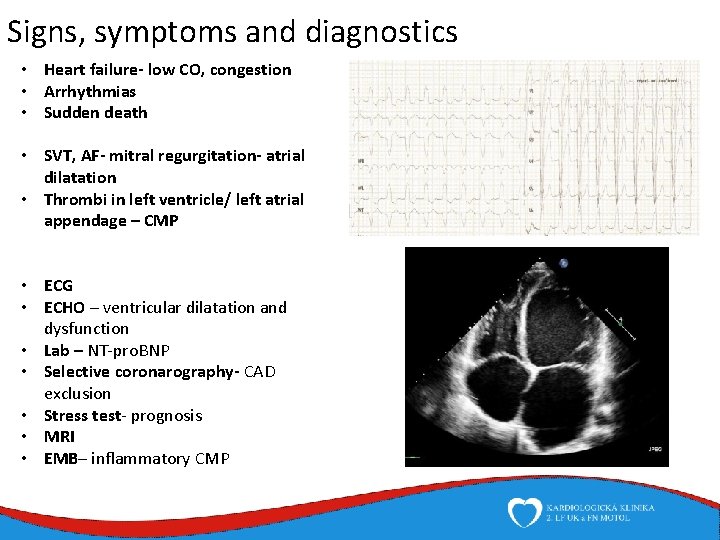

Signs, symptoms and diagnostics • Heart failure- low CO, congestion • Arrhythmias • Sudden death • SVT, AF- mitral regurgitation- atrial dilatation • Thrombi in left ventricle/ left atrial appendage – CMP • ECG • ECHO – ventricular dilatation and dysfunction • Lab – NT-pro. BNP • Selective coronarography- CAD exclusion • Stress test- prognosis • MRI • EMB– inflammatory CMP